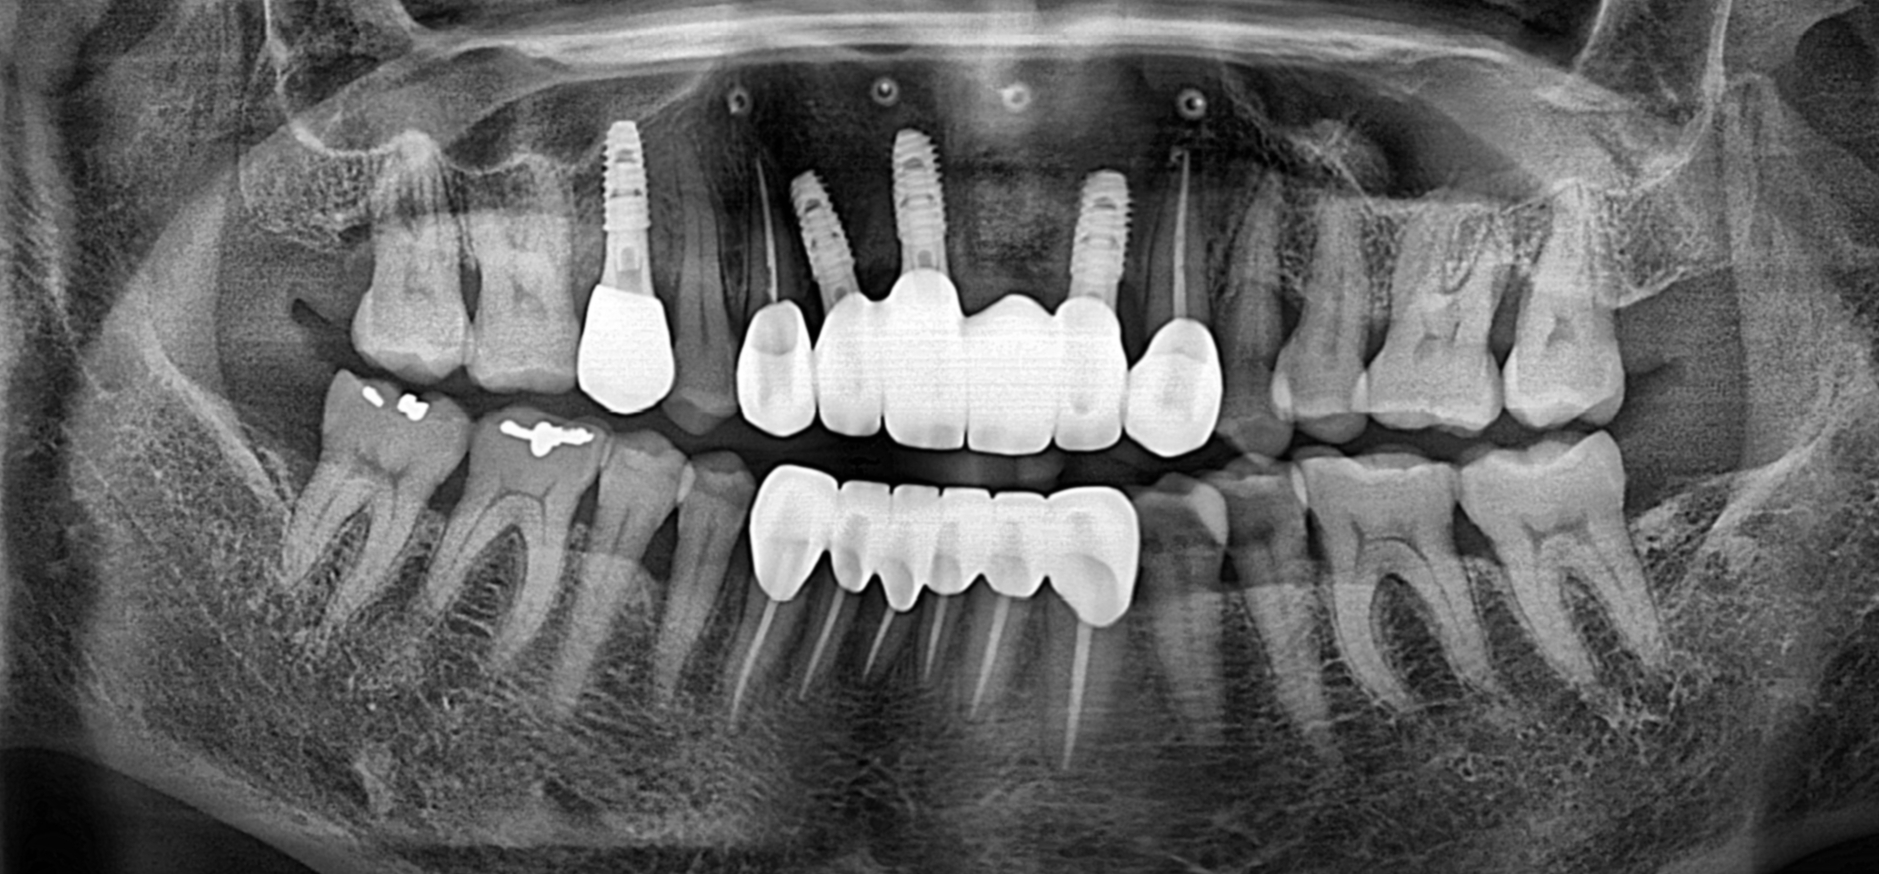

임플란트 치료를 진행 하려고 하는 부분들을 파노라마 상으로 보게 되면

잇몸뼈들이 다 녹아 패여 있는 모습들을 볼 수 있는데요 뼈이식과 함께 진행 하였습니다.

임플란트가 제대로 식립되려고 하면 치아를 제대로 지지하는 잇몸뼈처럼

임플란트도 제대로 지지 가능한 잇몸뼈가 필요합니다.

뼈이식 이후 잇몸뼈가 제대로 결합될때까지 길게는 6개월 이상 보통은 2~3개월 소요됩니다.

이 환자분은 상악의 임플란트 뼈이식 이후 최종 보철까지는 4개월 정도 소요 되었습니다.

최종 치료 완료 파노라마 사진 입니다.

위의 사진과 비교 하였을때 뼈이식으로 잇몸이 채워진 부분들도 확인 할 수 있습니다.